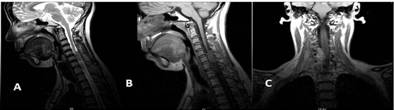

Con el estudio histopatológico se confirmaron los diagnósticos imagenológicos de sospecha, excepto los de malformación arteriovenosa y tumor neurógeno: en el primer caso no se requirió intervención quirúrgica y en el segundo, uno de los pacientes no pudo ser operado, mientras que en el otro no hubo confirmación y se diagnosticó un linfoma (fig. 2).

Cabe destacar que el estudio histopatológico posibilitó confirmar los siguientes diagnósticos imagenológicos de sospecha: quiste dermoide o lipoma, fibrosis, infiltración metastásica por tumor primario conocido y vascular, así como todos los meningiomas operados; sin embargo, no sucedió así con los diagnósticos de malformación arteriovenosa y tumor neurógeno: en el primer caso no se requirió intervención quirúrgica y en el segundo uno de los pacientes no pudo ser operado, mientras que en el otro no hubo confirmación y se diagnosticó un linfoma.